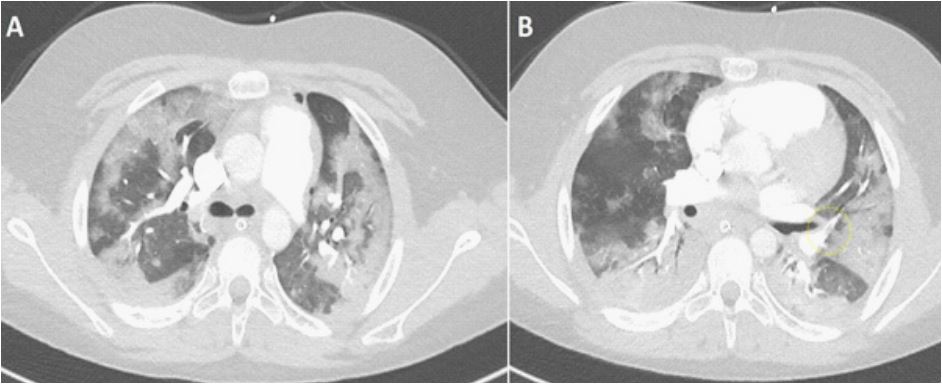

COVID-19 was confirmed with a RT-PCR test. Blood cultures and sputum cultures remained negative. On day 6 after hospital admission he was extubated and weaned off supplemental oxygen. On day 10 after admission he was transferred back to the referring hospital. He was re-admitted on day 14 due to respiratory deterioration, tachypnea with a respiratory rate of 30/minute, with need for High Flow Nasal Oxygen (HFNO) therapy 60 l/min and O2 of 60%. Piperacillin-tazobactam was started because of suspected hospital-acquired pneumonia. CRP increased to maximally 344 mg/L (Figure 2 and 3 for the course of the inflammatory parameters for both admissions). Pulmonary CT-scan showed bilateral pleural effusions (Figure 4A). Pre-existent ground glass opacities had now become consolidations with cavitation suggestive of Necrotising Pneumonia (NP) (Figure 4B). The pulmonary embolisms were diminished (Figure 4C).

Figure 4: (A-C) CT scan at time of deterioration.